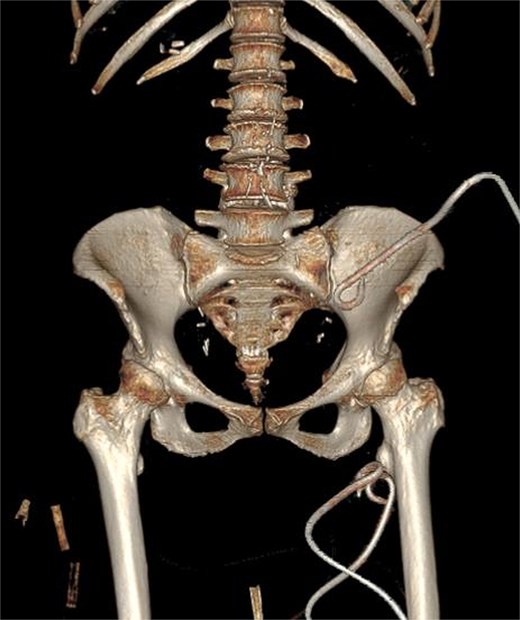

Contrast-enhanced CT demonstrated a large multiloculated IPA extending distally along the psoas sheath into the upper thigh, involving the adductor compartment (Fig. 1).

CT demonstrates multiloculated IPA with distal extension into the thigh adductor compartment. (A) Coronal CT showing a multiloculated IPA. (B) Axial CT demonstrating the psoas collection. (C) Coronal CT illustrating distal extension along the psoas sheath into the adductor compartment. (D) Axial CT of the thigh confirming distal involvement.